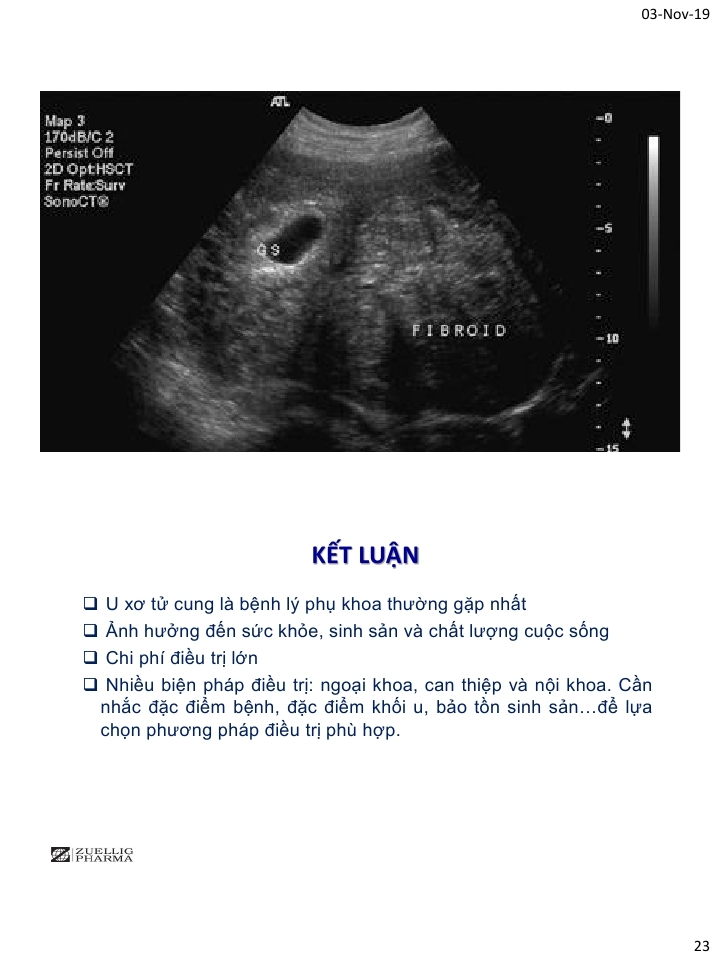

Thách thức và quan điểm đương đại trong điều trị u xơ tử cung